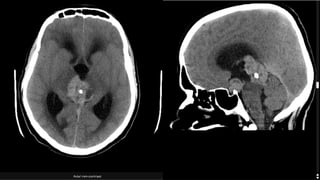

CT Findings

• High cellular tumor

• Slight hyperdense mass, somehow lobulated

• Avidly enhancing post contrast

• Characteristically “engulfs” the pineal gland and promotes its

calcification, resulting in a central of calcification.

• #17 A large lobulated mass is centered on the pineal gland, engulfing the pineal calcifiation. It is somewhat hyperdense compared to adjacent brain. A further smaller mass is seen in the floor of the third ventricle. The midbrain is distorted, compressed and demonstrates low density suggestive of edema. Obstructive hydrocephalus is present.  Pineal germinoma with a synchronous suprasellar germ cell tumor